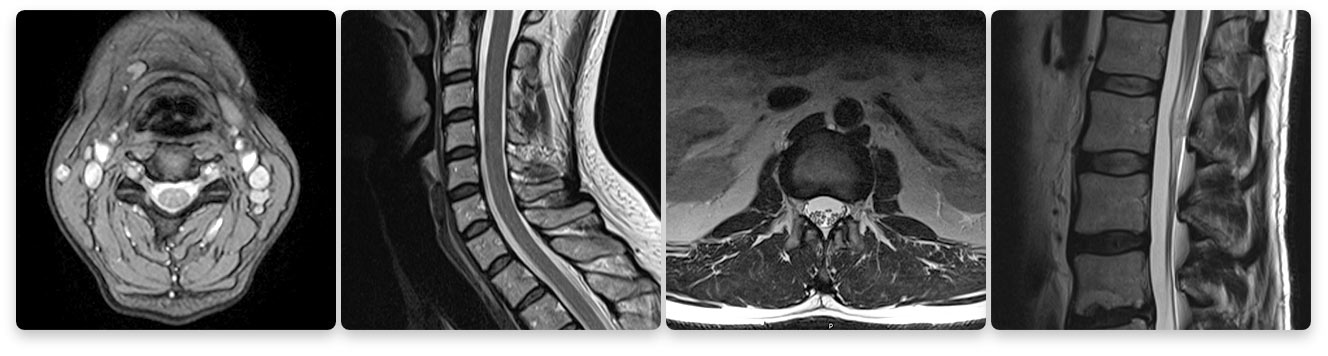

Texas Health Southlake's Imaging Department's 1.5T High Definition MRI Images

Seeing is believing. Do not compromise quality for a lower price. The images above compare a low strength machine to our 1.5T high-field machine. Two of the biggest factors that contribute to MRI image quality are strength of the magnet and skill of the technologist.

Beware of MRIs with lower magnet or tesla strength (Tesla is a measurement of magnetic field strength). The gold standard of MRI today is a 1.5T (T stands for tesla) strength MRI because it produces extremely clear images for a very accurate diagnosis. A lower-strength MRI produces images where the quality is much lower. You want to take care that you are not compromising your diagnosis when choosing an MRI.

1.5 tesla indicates the field-strength of the magnet used to obtain the images – the higher the field-strength, the more clear or detailed the images. A radiologist is looking to obtain the highest level of clarity for the most accurate diagnosis. Think of a spine injury. Let’s use, for example, a bulging disk. An MRI will show the anatomy of the vertebrae as well as the disks, spinal cord and the spaces between the vertebrae through which nerves pass. With such a complex image, your doctor will want the most clear, distinct picture so they can accurately assess the injury and make the proper diagnosis for treatment. The strength of the magnet is extremely important to achieve this clarity.

Lower strength means a less detailed image. The physician will have a harder time diagnosing the problem if he or she is looking at a low-quality image. These scans often take longer, making the patient more susceptible to movement resulting in reduced image quality. Lower image quality may lead to a longer wait time for the physician to read the scan or even misdiagnoses. Often prior to therapy, the entire scan may need to be redone. This costs you and your insurance company more money and may delay your diagnosis and treatment.